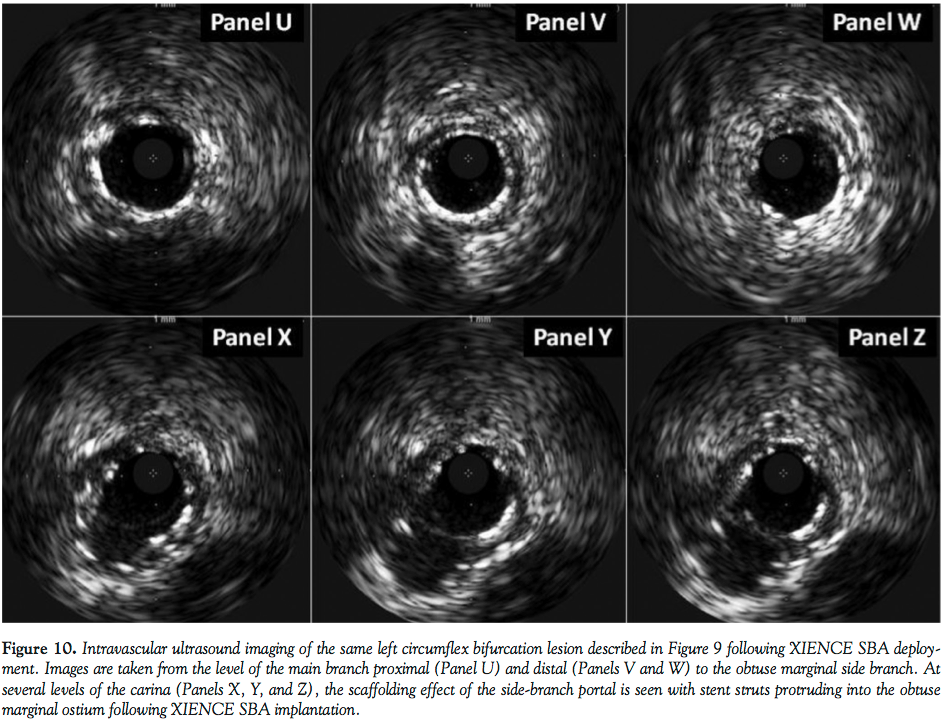

Figure 9 is the first XIENCE SBA implantation to be performed as part of a live

case demonstration course (The 16th Annual Warsaw Course on Cardiovascular Interventions). Panels Q and R illustrate not only the lesion severity at the level of the bifurcation in this right-angle takeoff left circumflex coronary artery, but also demonstrate the ability to negotiate the device around angulated vessel geometry, after thorough vessel preparation with balloon therapy has been performed. The left circumflex was designated as the MB for the purposes of this implant and the

obtuse marginal considered the SB into which the portal opening was deployed. The orientation of XIENCE SBA during inflation is inset into Panel Q. Following high-pressure dilation, the final result is noted in both left anterior oblique caudal and anteroposterior caudal views (Panels S and T). Intravascular ultrasound (IVUS) assessment following final XIENCE SBA inflation is demonstrated in Figure 10, showing the MB proximal (Panel U) and distal (Panels V and W) to the obtuse marginal SB. The sonographic appearance of the portal opening into the SB is appreciated at various levels of the carina (Panels X, Y, and Z) demonstrating ostial SB coverage provided by this 1-2 mm aperture.